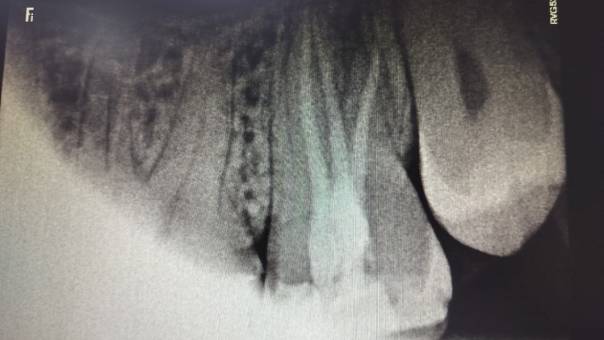

Clinical Outcome:

The procedure was done comfortably and successfully

on the patient, and recovery was smooth. At

follow-up visits, he reported complete relief from

pain, and healing was progressing as expected.

After Obturation